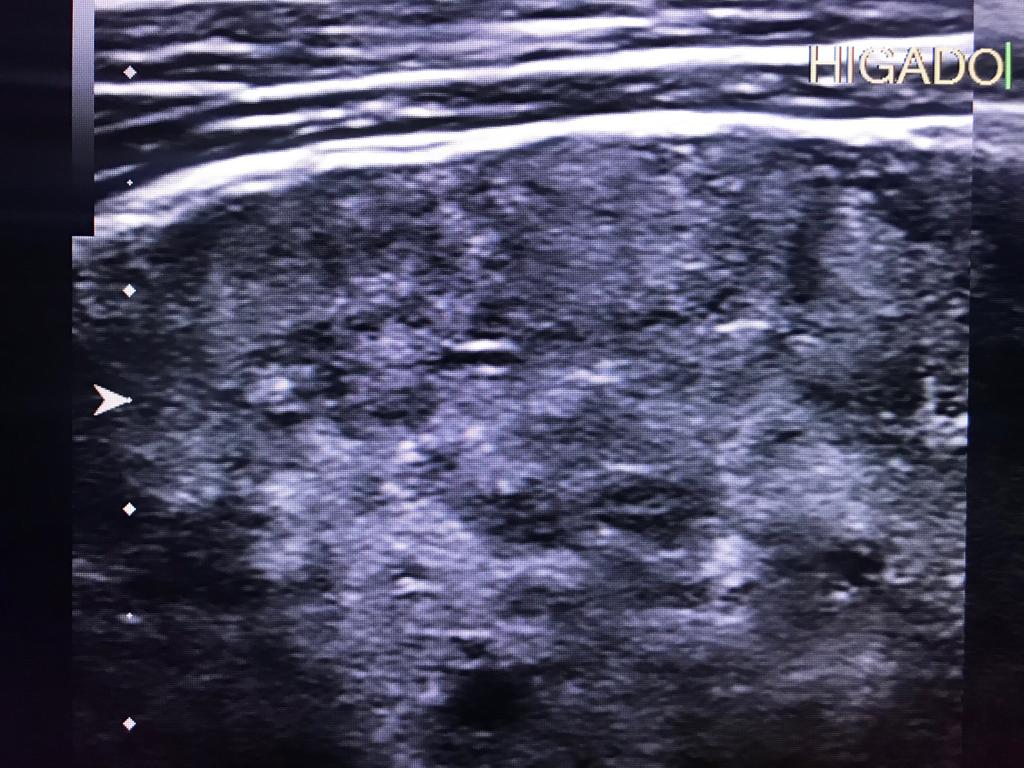

Masculino de 52 años, con cirrosis hepática. La elastografía ecográfica evidencia fibrosis Categoría F3 según escala de METAVIR y la presencia de múltiples nodulaciones, que en su mayoría son menores a 2 cm.

En este contexto, toda nodulación mayor de 1 cm, debe ser evaluada idealmente con RM trifásica con secuencia de Difusión , para discriminar si se trata de nódulos de regeneración , nódulos displásicos o hepatocarcinoma.

En el presente caso, encontramos una lesión típica de hepatocarcinoma en el segmento 5 ( hiperintensa en T2, restringe en la Difusión con ADC bajo. Realza heterogéneamente postcontraste EV, con wash out y presencia cápsula tardía).

El objetivo es identificar dentro de la multifocalidad de nódulos , un hepatocarcinoma precoz o de pequeño tamaño , cuando la posibilidad de tratamiento con intención curativa es viable , a pesar de la cirrosis.